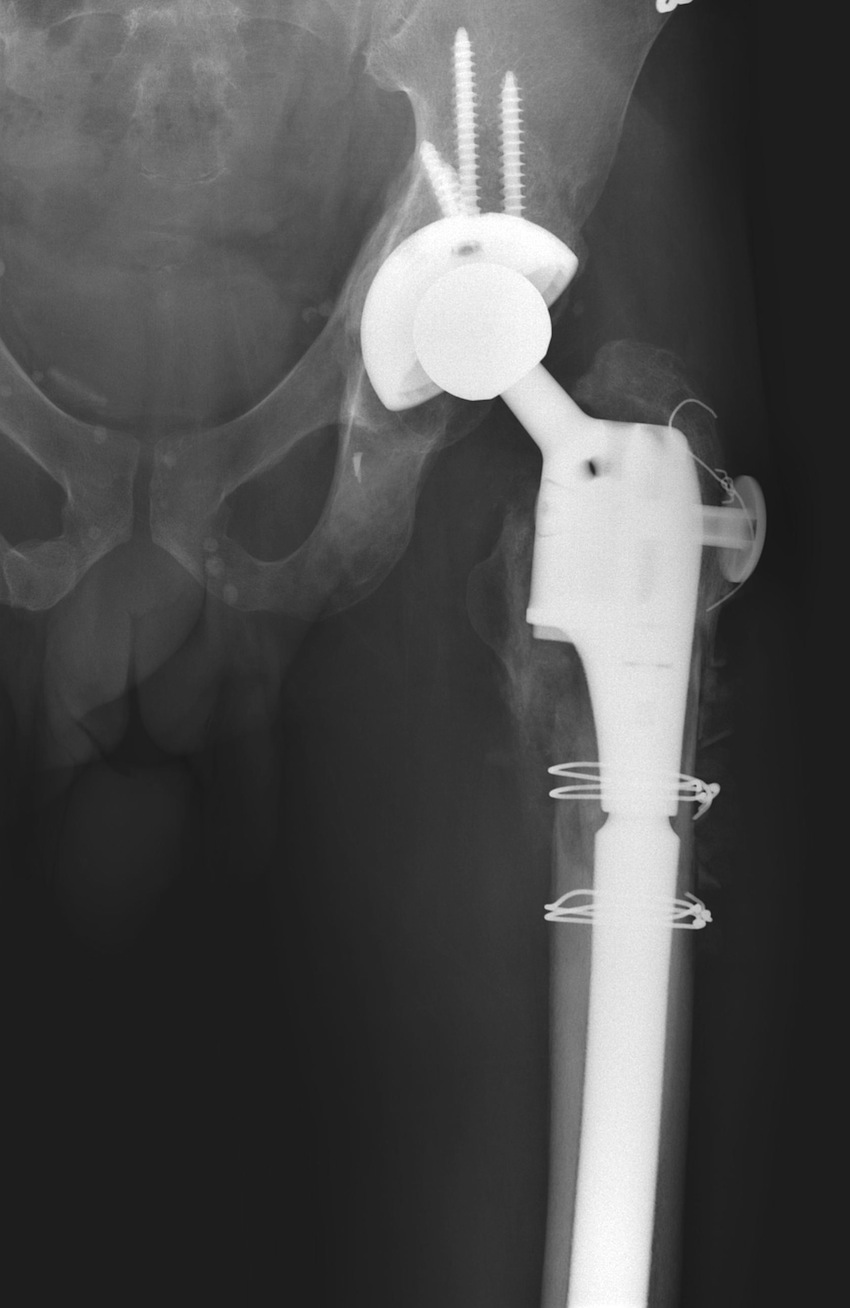

3. Modular diaphyseal fitting, proximal filling uncemented stem

Design

- press fit metaphyseal segment

- slotted diaphyseal segment

- initial stability through distal fixation

Indications

- Paprosky Types I – IIIB